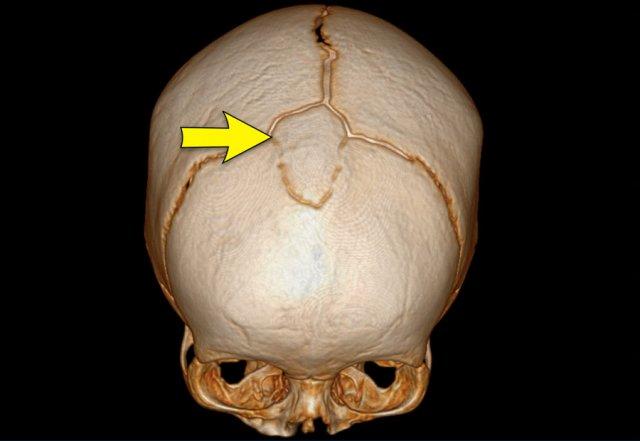

Đầu lệch sau do dính khớp (Synostotic posterior plagiocephaly)

Trong trường hợp này, đường khâu lambda đã đóng sớm.

Đây là chẩn đoán phân biệt chính với đầu lệch do tư thế (xem phần trên).

Có nguy cơ dị dạng Chiari loại 1 và nên chụp MRI não cùng khớp nối sọ-cổ.

Hình ảnh

Dính khớp đường khâu lambda bên phải.

Phình lồi vùng chẩm-đỉnh đối bên rõ ràng.